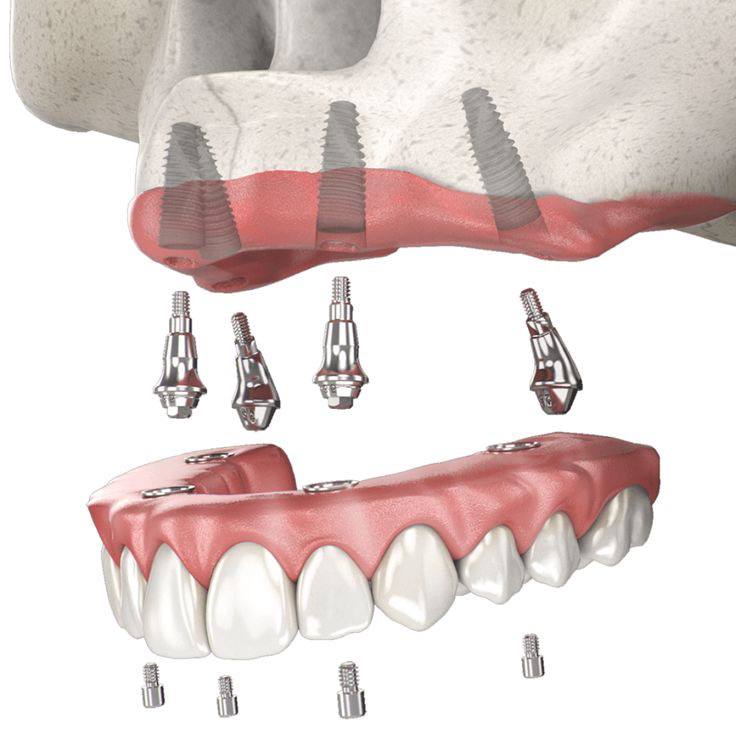

ایمپلنت کامل دهان، که با عنوان «ایمپلنت کامل فک بالا و پایین» نیز شناخته می شود، یکی از کارآمدترین روش های بازسازی کامل دهان برای بیمارانی است که تمام یا بخش عمده ای از دندان های خود را از دست داده اند. در این روش، مجموعه ای از پروتزهای ثابت بر پایهٔ چند فیکسچر در استخوان فک انسان قرار می گیرند و جایگزینی پایدار و بادوام برای دندان های طبیعی فراهم می کنند. یکی از رایج ترین رویکردها در این زمینه، تکنیک All-on-6 است که با استفاده از شش فیکسچر استراتژیک، امکان حمایت کامل یک قوس دندانی را فراهم می کند و عملکرد جویدن و زیبایی لبخند بیمار را به شکل مؤثری باز می گرداند.

بر خلاف کاشت تکی هر دندان، در ایمپلنت کامل دهان از تعداد محدودی پایهٔ ایمپلنت استفاده می شود؛ به گونه ای که با کمترین تعداد فیکسچر، امکان حمایت کامل از یک قوس دندانی فراهم شود. این رویکرد علاوه بر کاهش هزینه و زمان درمان، سبب حداقل سازی مداخلات جراحی و افزایش سرعت بازگشت عملکرد دهانی بیمار می شود.

در ایمپلنت کامل فک، فیکسچرهای تیتانیومی به عنوان ریشه های مصنوعی در استخوان فک قرار می گیرند. پس از مرحله اُستئواینتگریشن، یعنی جوش خوردن ایمپلنت با استخوان، پروتز ثابت دندانی روی آنها نصب می شود تا عملکردی مشابه دندان طبیعی در جویدن، تکلم و زیبایی ایجاد شود.

استفاده از تکنیک All-on-6 در این روش باعث می شود شش پایه استراتژیک به طور بهینه در فک قرار گیرند، پایداری پروتز افزایش یابد و نیروهای جویدن به صورت یکنواخت توزیع شود.

تکنیک All-on-6 یکی از روش های پیشرفته بازسازی کامل فک است که در آن شش فیکسچر تیتانیومی یا آلیاژهای مقاوم مانند روکسولید در نواحی دارای بیشترین تراکم استخوانی قرار داده می شود. جایگذاری دقیق و استراتژیک این فیکسچرها امکان ایجاد تکیه گاهی پایدار برای یک پروتز ثابت کامل را فراهم می کند و موجب می شود نیروهای جویدن به طور یکنواخت در فک توزیع شود.

به دلیل تعداد بیشتر پایه ها، این روش نسبت به تکنیک All-on-4 پایداری بالاتری دارد و برای بیمارانی که از نظر کیفیت و حجم استخوان وضعیت نسبتاً مناسبی دارند، گزینه ای مطمئن تر محسوب می شود. استفاده از شش ایمپلنت، ثبات پروتز را افزایش داده و شرایطی فراهم می کند که بیمار بتواند با آسودگی غذا بخورد، صحبت کند و عملکرد دهانی طبیعی تری را تجربه کند.

در مقابل، تکنیک All-on-6 به دلیل برخورداری از شش فیکسچر، پایداری مکانیکی بالاتری ایجاد می کند و نیروهای جویدن را به شکل متعادل تری در سراسر قوس فکی توزیع می کند. این ویژگی، دوام سیستم پروتزی را افزایش داده و خطر وارد شدن فشار بیشازحد به یک ناحیه را کاهش می دهد. بنابراین، All-on-6 برای بیمارانی که حجم استخوان مناسب تری دارند یا نیاز به تکیه گاه قوی تر دارند، گزینه ای برتر است.

All-on-4: چهار فیکسچر تیتانیومی در فک (دو ایمپلنت قدامی عمودی و دو ایمپلنت خلفی با زاویهگذاری مناسب) قرار می گیرد.

All-on-6: شش فیکسچر در نقاط استراتژیک فک برای پایداری بیشتر پروتز نصب می شوند.

جراحی کاشت ایمپلنت معمولاً در یک جلسه انجام می شود و دقت بالا در جایگذاری ایمپلنت ها ضروری است، زیرا کوچک ترین خطا می تواند موفقیت درمان را کاهش دهد.